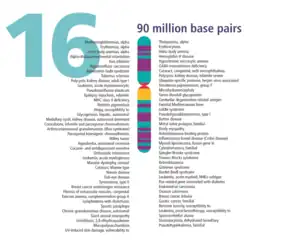

En 1992, le gène de la maladie est localisé sur le bras court du chromosome 16[12]. En 1997, deux groupes de recherches identifient simultanément et séparément le gène de la maladie (identification de sa séquence génétique)[13].

Génétique

Le gène en cause est le gène MEFV (pour MEditerranean FeVer)[17] qui code une protéine, dite marénostrine (du nom latin de la méditerranée mare nostrum) ou pyrine (du grec feu, fièvre pyros), impliquée dans les processus inflammatoires[18] (activation de l'inflammasome)[1].

Ce gène a été identifié en 1997 par un consortium français[19]. Ce dernier a bénéficié d'une collaboration entre le programme Généthon et des partenaires turcs et tunisiens et de la participation d'un grand nombre de familles atteintes dans ces pays. Différentes mutations de ce gène apparaissent en effet chez 85 % des patients provenant de populations méditerranéennes. En parallèle, un autre collectif de chercheurs israéliens, américains et australiens identifiait également le lien entre ce gène et la maladie[20].